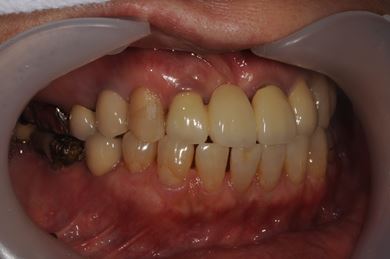

骨再生スピードインプラント治療+セラミック治療

| 治療方針 | 骨再生法によりインプラント治療を可能にする。抜歯と同時にインプラント埋入を行い、治療期間を短縮する。 | ||||||||||||||||||||||||||||||||

| 治療内容 | インプラント3本(抜歯即日スピードインプラント、GBR)、メタルボンドセラミッククラウン4本 | ||||||||||||||||||||||||||||||||